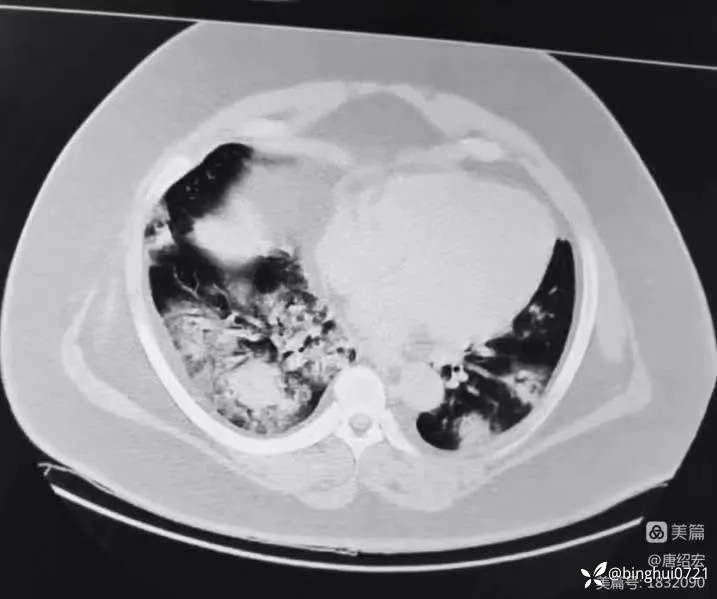

军团菌肺炎的典型CT表现及治疗

男,36 岁,主诉间断发热 1 周,咳嗽伴气短 3 天。入院CT如下:

军团菌肺炎

行肺泡灌洗液 NGS:嗜肺军团菌 3262 条,咽峡炎链球菌 20 条(考虑定植),金葡菌 10 条(考虑鼻咽部向下污染)。